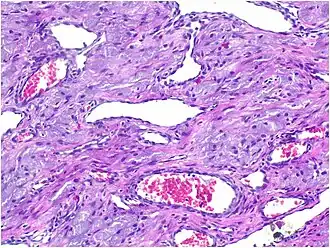

Histopathological Characteristics

Histopathologically, congenital epulis is usually characterized by the presence of big, rounded cells that fill the mucosa's lamina propria and have round to oval nuclei and an abundance of eosinophilic cytoplasm.[10] A thin layer of connective tissue separated the surface layer of cells from the growing new cells. Numerous histological traits, such as a fibrous and granulomatous appearance, have been reported in recent research.[10]

The most common theory about how these lesions form is that they come from early-stage connective tissue cells that change due to external factors affecting their genes.[11]

Microscopically, congenital epulis is composed of:

- Sheets of proliferating polygonal to round cells with overlying thin squamous, eosinophilic, granular cytoplasm[12][13]

- Centrally located, round nuclei [7]

These histopathological features are essential in distinguishing congenital epulis from other gingival and soft tissue neoplasms.